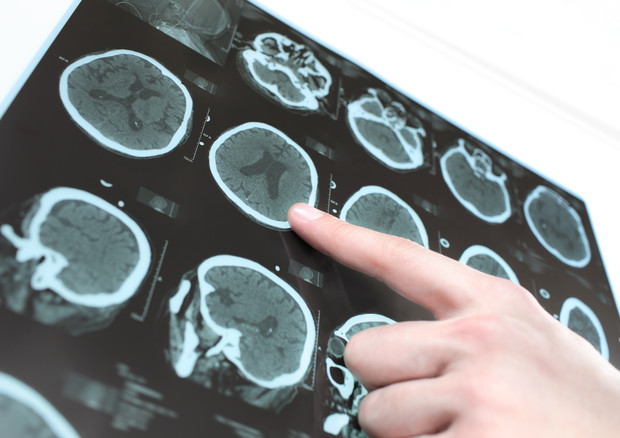

La causa di questa malattia neurodegenerativa è la presenza anomala, nel cervello, di aggregati della proteina alfa-sinucleina, che porta alla morte selettiva dei neuroni produttori di dopamina. Spesso, nel momento in cui si riceve la diagnosi, oltre il 60% delle cellule dopaminergiche sono già degenerate.